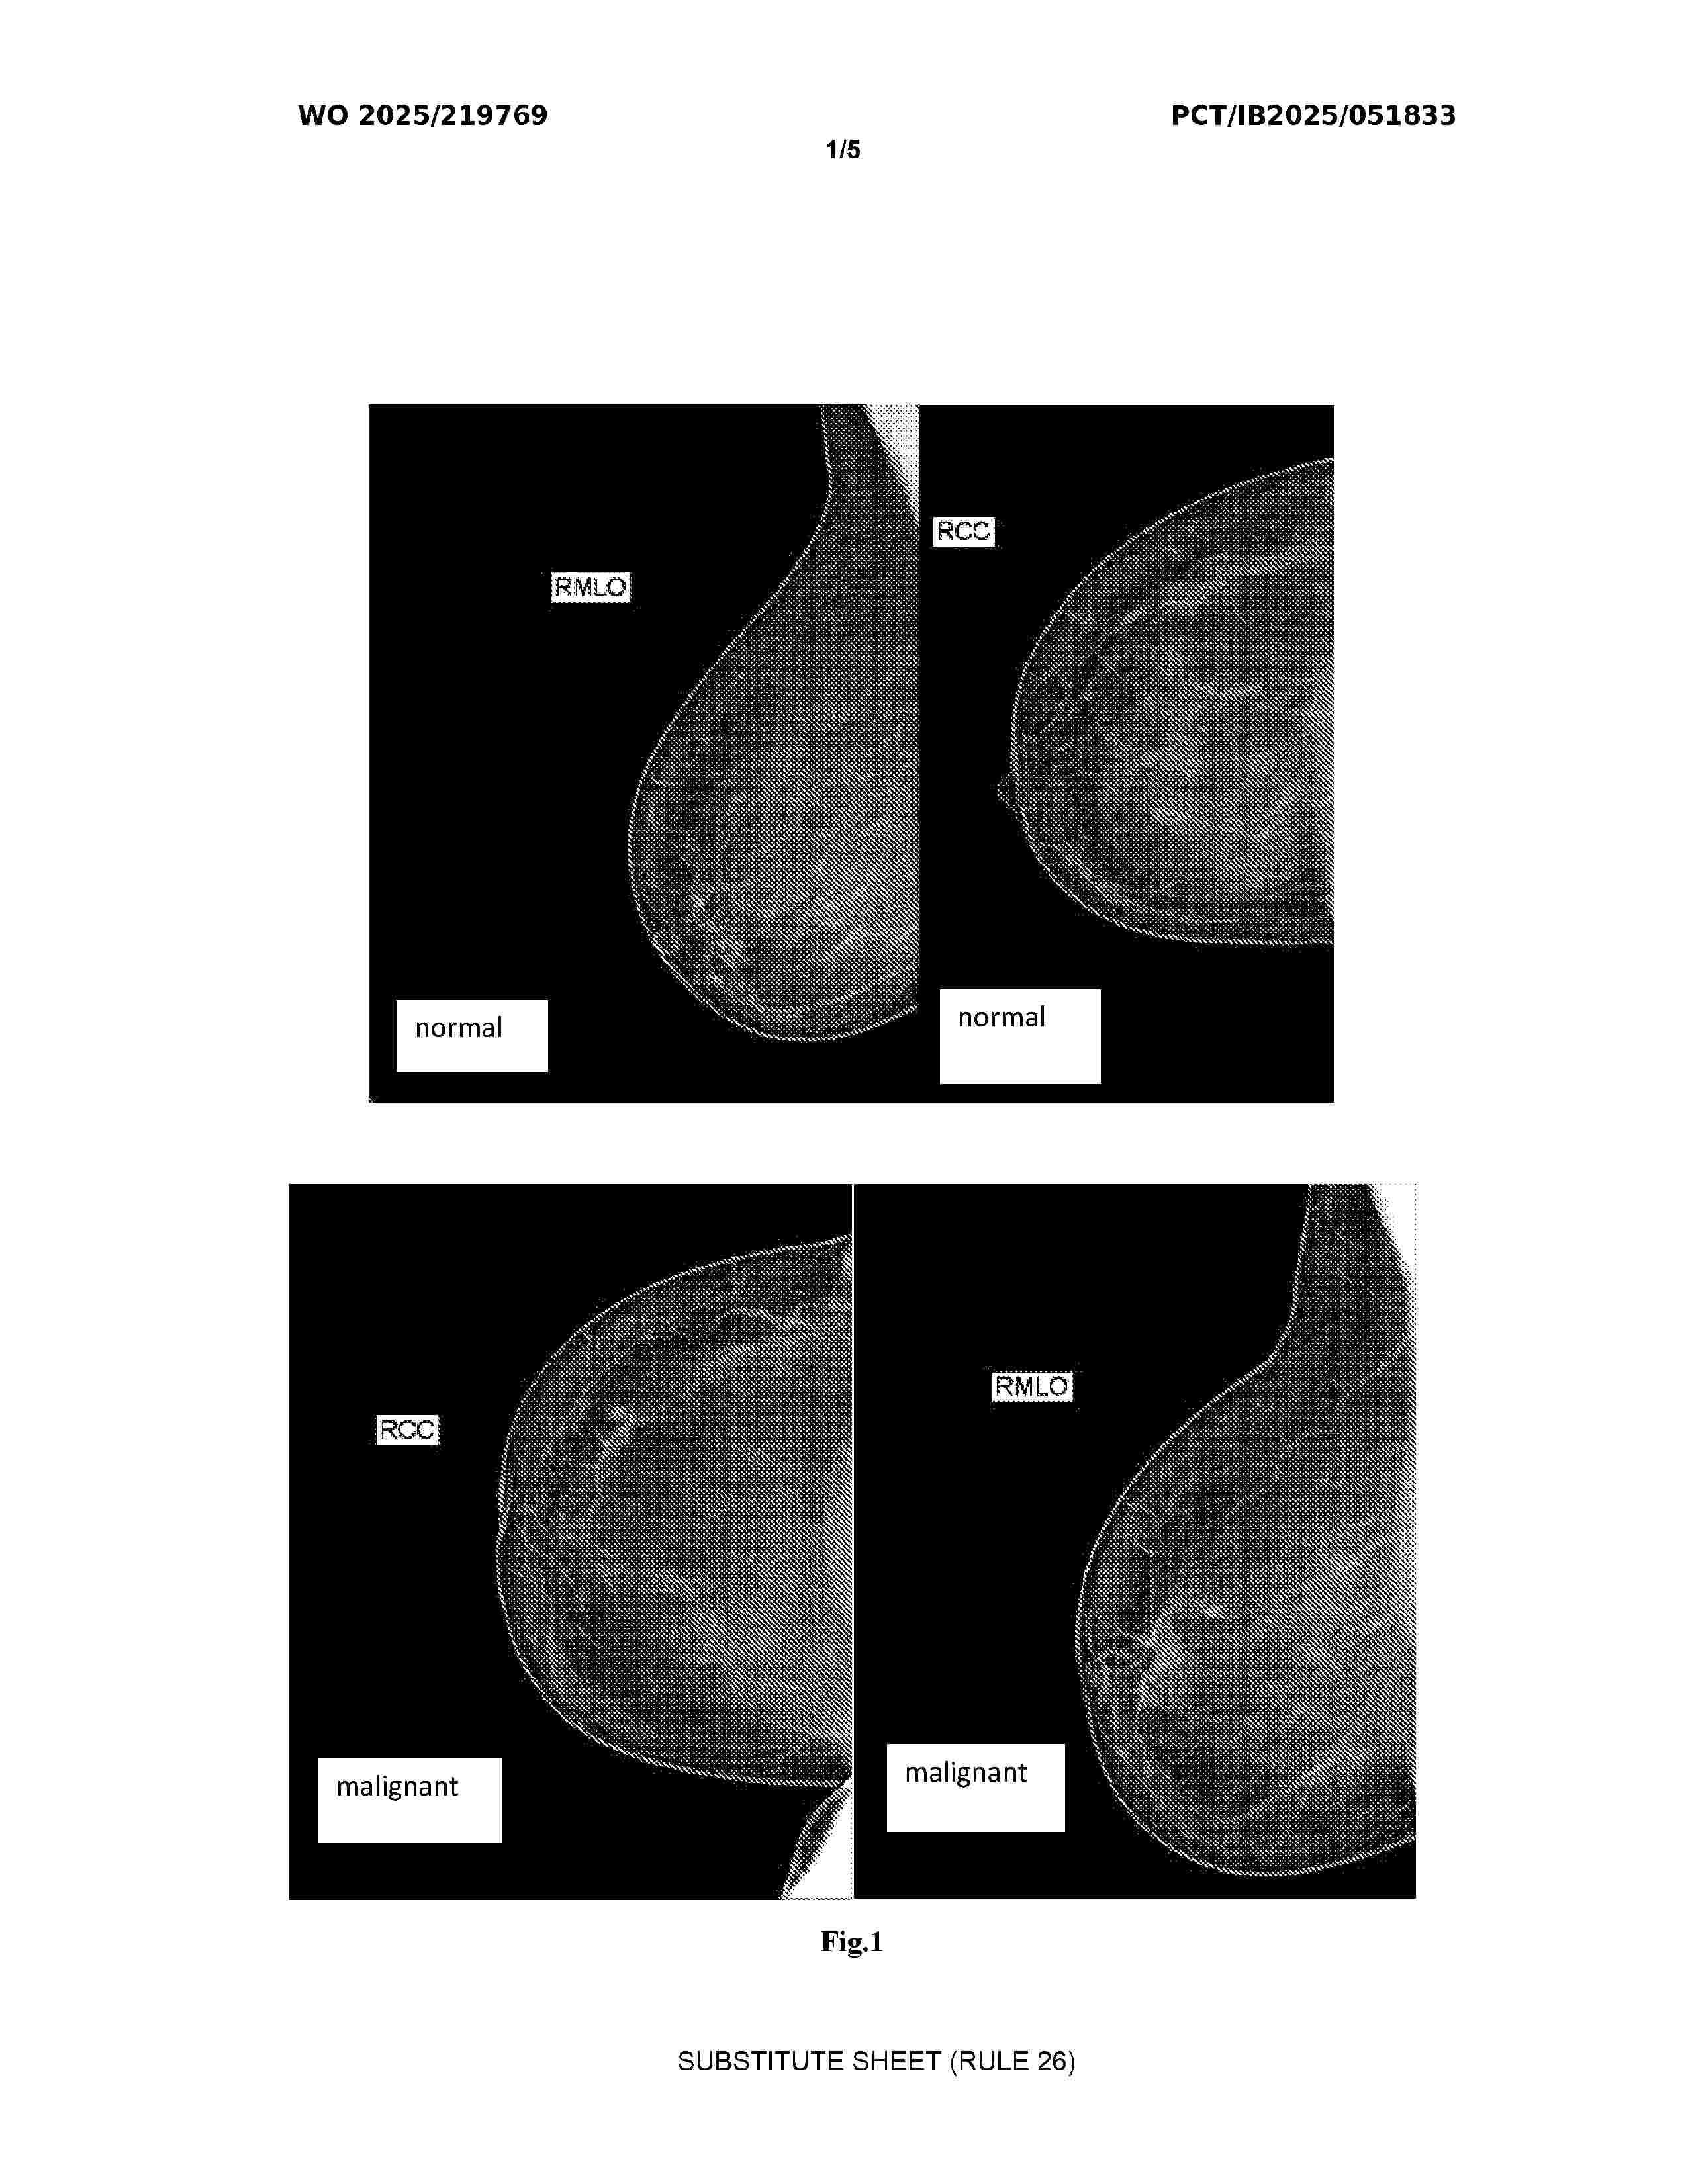

AI-BASED SMART HEALTH SCREENING SYSTEM FOR IDENTIFYING INDIVIDUALS AT RISK OF DEVELOPING CANCERS, CARDIOVASCULAR DISEASE AND TYPE 2 DIABETES

Nº publicación: WO2025219769A1 23/10/2025

Solicitante:

AVAN AMIR [IR]

AVAN, Amir

Resumen de: WO2025219769A1

The invention is an AI-driven health screening system for early detection of cancers, cardiovascular diseases, and type 2 diabetes. It integrates multiple screening methods, using machine learning, deep learning, and natural language processing to analyze genetic and health data. A federated learning framework ensures high prediction accuracy while maintaining data privacy. The system also employs a blockchain-based electronic health record (EHR) for secure data management. AI models, including neural networks and support vector machines, assess risk factors and provide personalized healthcare recommendations. Designed with a three-tier architecture, it supports deployment as a web service, software, or integration into existing programs. The system enhances early disease detection, optimizes healthcare resources, and improves patient outcomes by offering a scalable, efficient, and non-invasive screening solution.